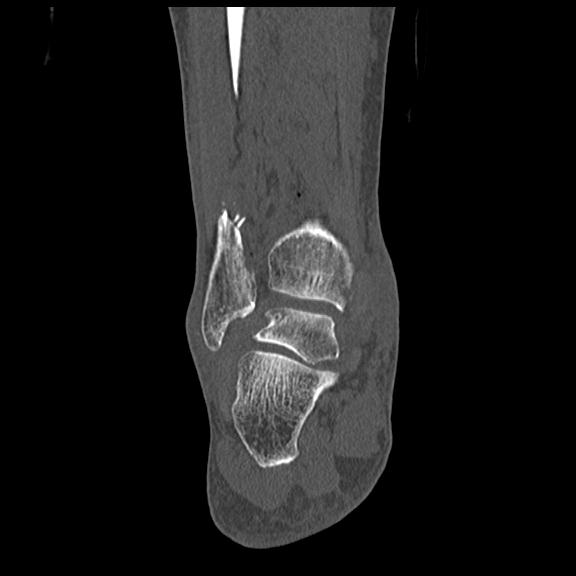

102755 1/4 2R 1/15 2R 右足関節 68歳女性 右三果脱臼骨折

56476 8/28 4R 1/21 2R 左足関節 デジカメ写真 72歳女性 右足関節AS